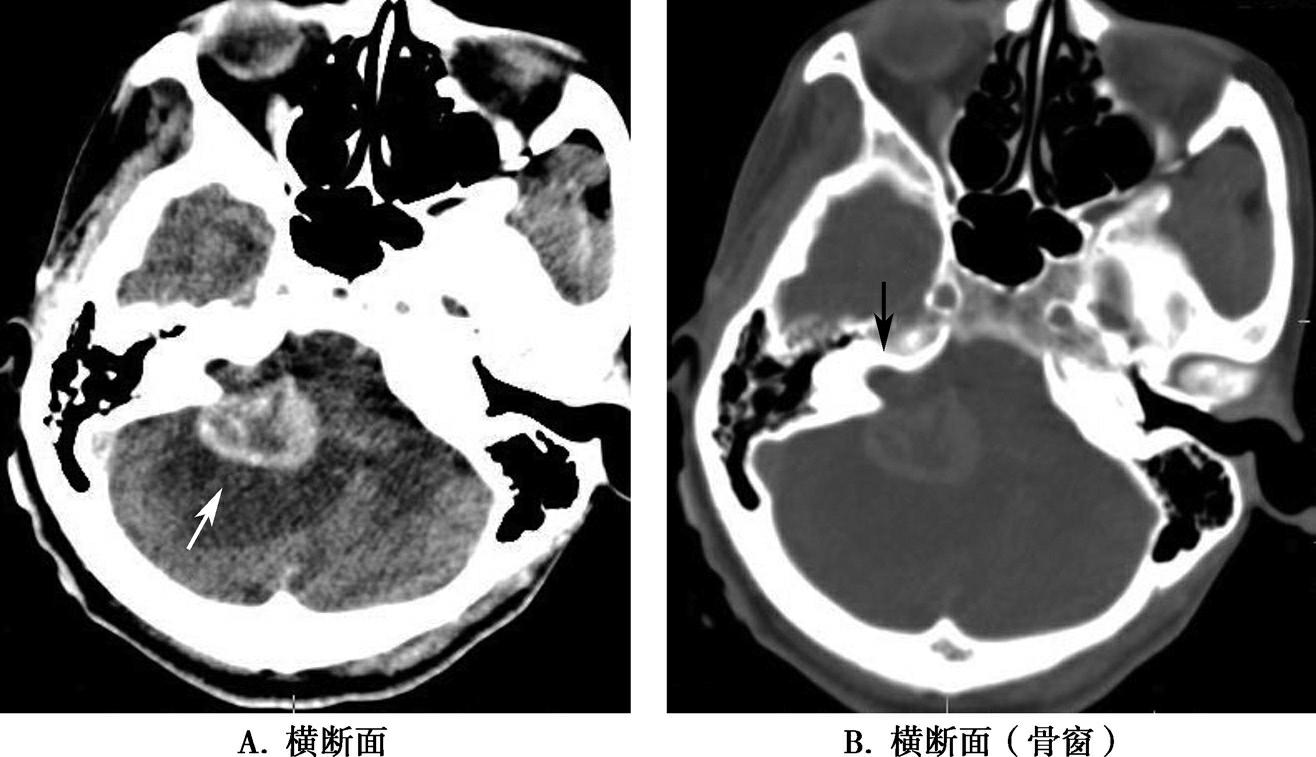

破裂孔、卵圆孔、棘孔及斜坡等均为重要的解剖结构,临床常见疾病如鼻咽癌常侵犯上述结构(图1-2-3)。颈静脉孔区较常见的肿瘤为颈静脉球瘤,常伴有颈静脉孔及其邻近骨质的破坏(图1-2-4)。

图1-2-3 鼻咽癌颅底骨质破坏

A.横断面;B.横断面(骨窗)

骨窗示左侧岩尖、斜坡、左侧蝶骨大翼骨质破坏、受侵(白箭),肿瘤经破裂孔侵入颅内(黑箭头)

图1-2-4 右侧颈静脉球瘤

A.横断面(骨窗);B.横断面

右侧颈静脉孔区不规则骨质破坏(箭),局部见软组织肿块(☆)